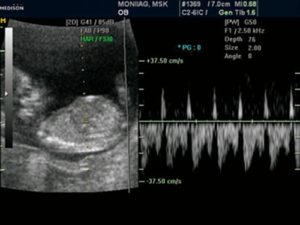

Допплерометрия — это один из методов ультразвуковой диагностики, позволяющий оценить интенсивность кровотока в различных сосудах, например, в сосудах матки и пуповины. Наиболее информативна она после 30 недели, но при отклонениях в течении беременности (например, при отставании плода в развитии) допплер УЗИ может назначаться и раньше — начиная с 20 недели.

Допплерометрия – это визуальная оценка кровотока (когда узистом с экрана монитора наблюдается цветовое и графическое изображение кривых скоростей кровотока).

Допплерография – это та же допплерометрия, только дополнительно ещё ведётся запись показаний на ленте, чтобы проследить за изменением (улучшением/ухудшением) кровотока после проведённого лечения.

Наиболее полноценную картину кровообращения между маткой и плодом получают при допплерографическом исследовании, которое проводится всем женщинам трижды за срок беременности.

Методика позволяет:

- измерить кровоток по скорости движения форменных элементов;

- определить его направление в артериях и венах;

- зафиксировать изменения до клинических проявлений.

Эффект основан на свойствах отражения ультразвуковой волны, совершенно безопасен для ребенка и матери

Все изменения регистрируются на мониторе, замеряются специальными датчиками, могут фотографироваться в необходимом формате.